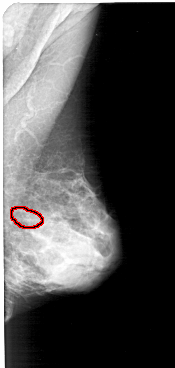

A_1570_1.RIGHT_MLO

RIGHT_MLO LINES 5146 PIXELS_PER_LINE 2446 BITS_PER_PIXEL 12 RESOLUTION 43.5 OVERLAY

FILE: A_1570_1.RIGHT_MLO.OVERLAY

TOTAL_ABNORMALITIES 1

ABNORMALITY 1

LESION_TYPE CALCIFICATION TYPE PLEOMORPHIC DISTRIBUTION CLUSTERED

ASSESSMENT 4

SUBTLETY 1

PATHOLOGY MALIGNANT

TOTAL_OUTLINES 1

BOUNDARY